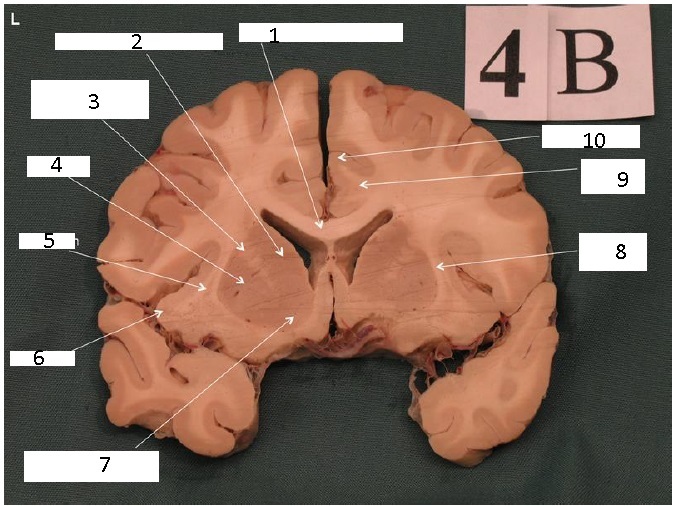

Identify 1

Body of Corpus Callosum

Identify 2

Cingulate Gyrus

Head of Caudate Nucleus

Identify 3

Anterior Limb of the Internal Capsule

Identify 4

Putamen

Identify 5

Claustrum

Identify 6

Insula

Identify 7

Nucleus Accumbens

Identify 8

External Capsule

the lateral portion of the ‘A’ formed by the external and internal capsule

Identify 9

Cingulum

Identify 10